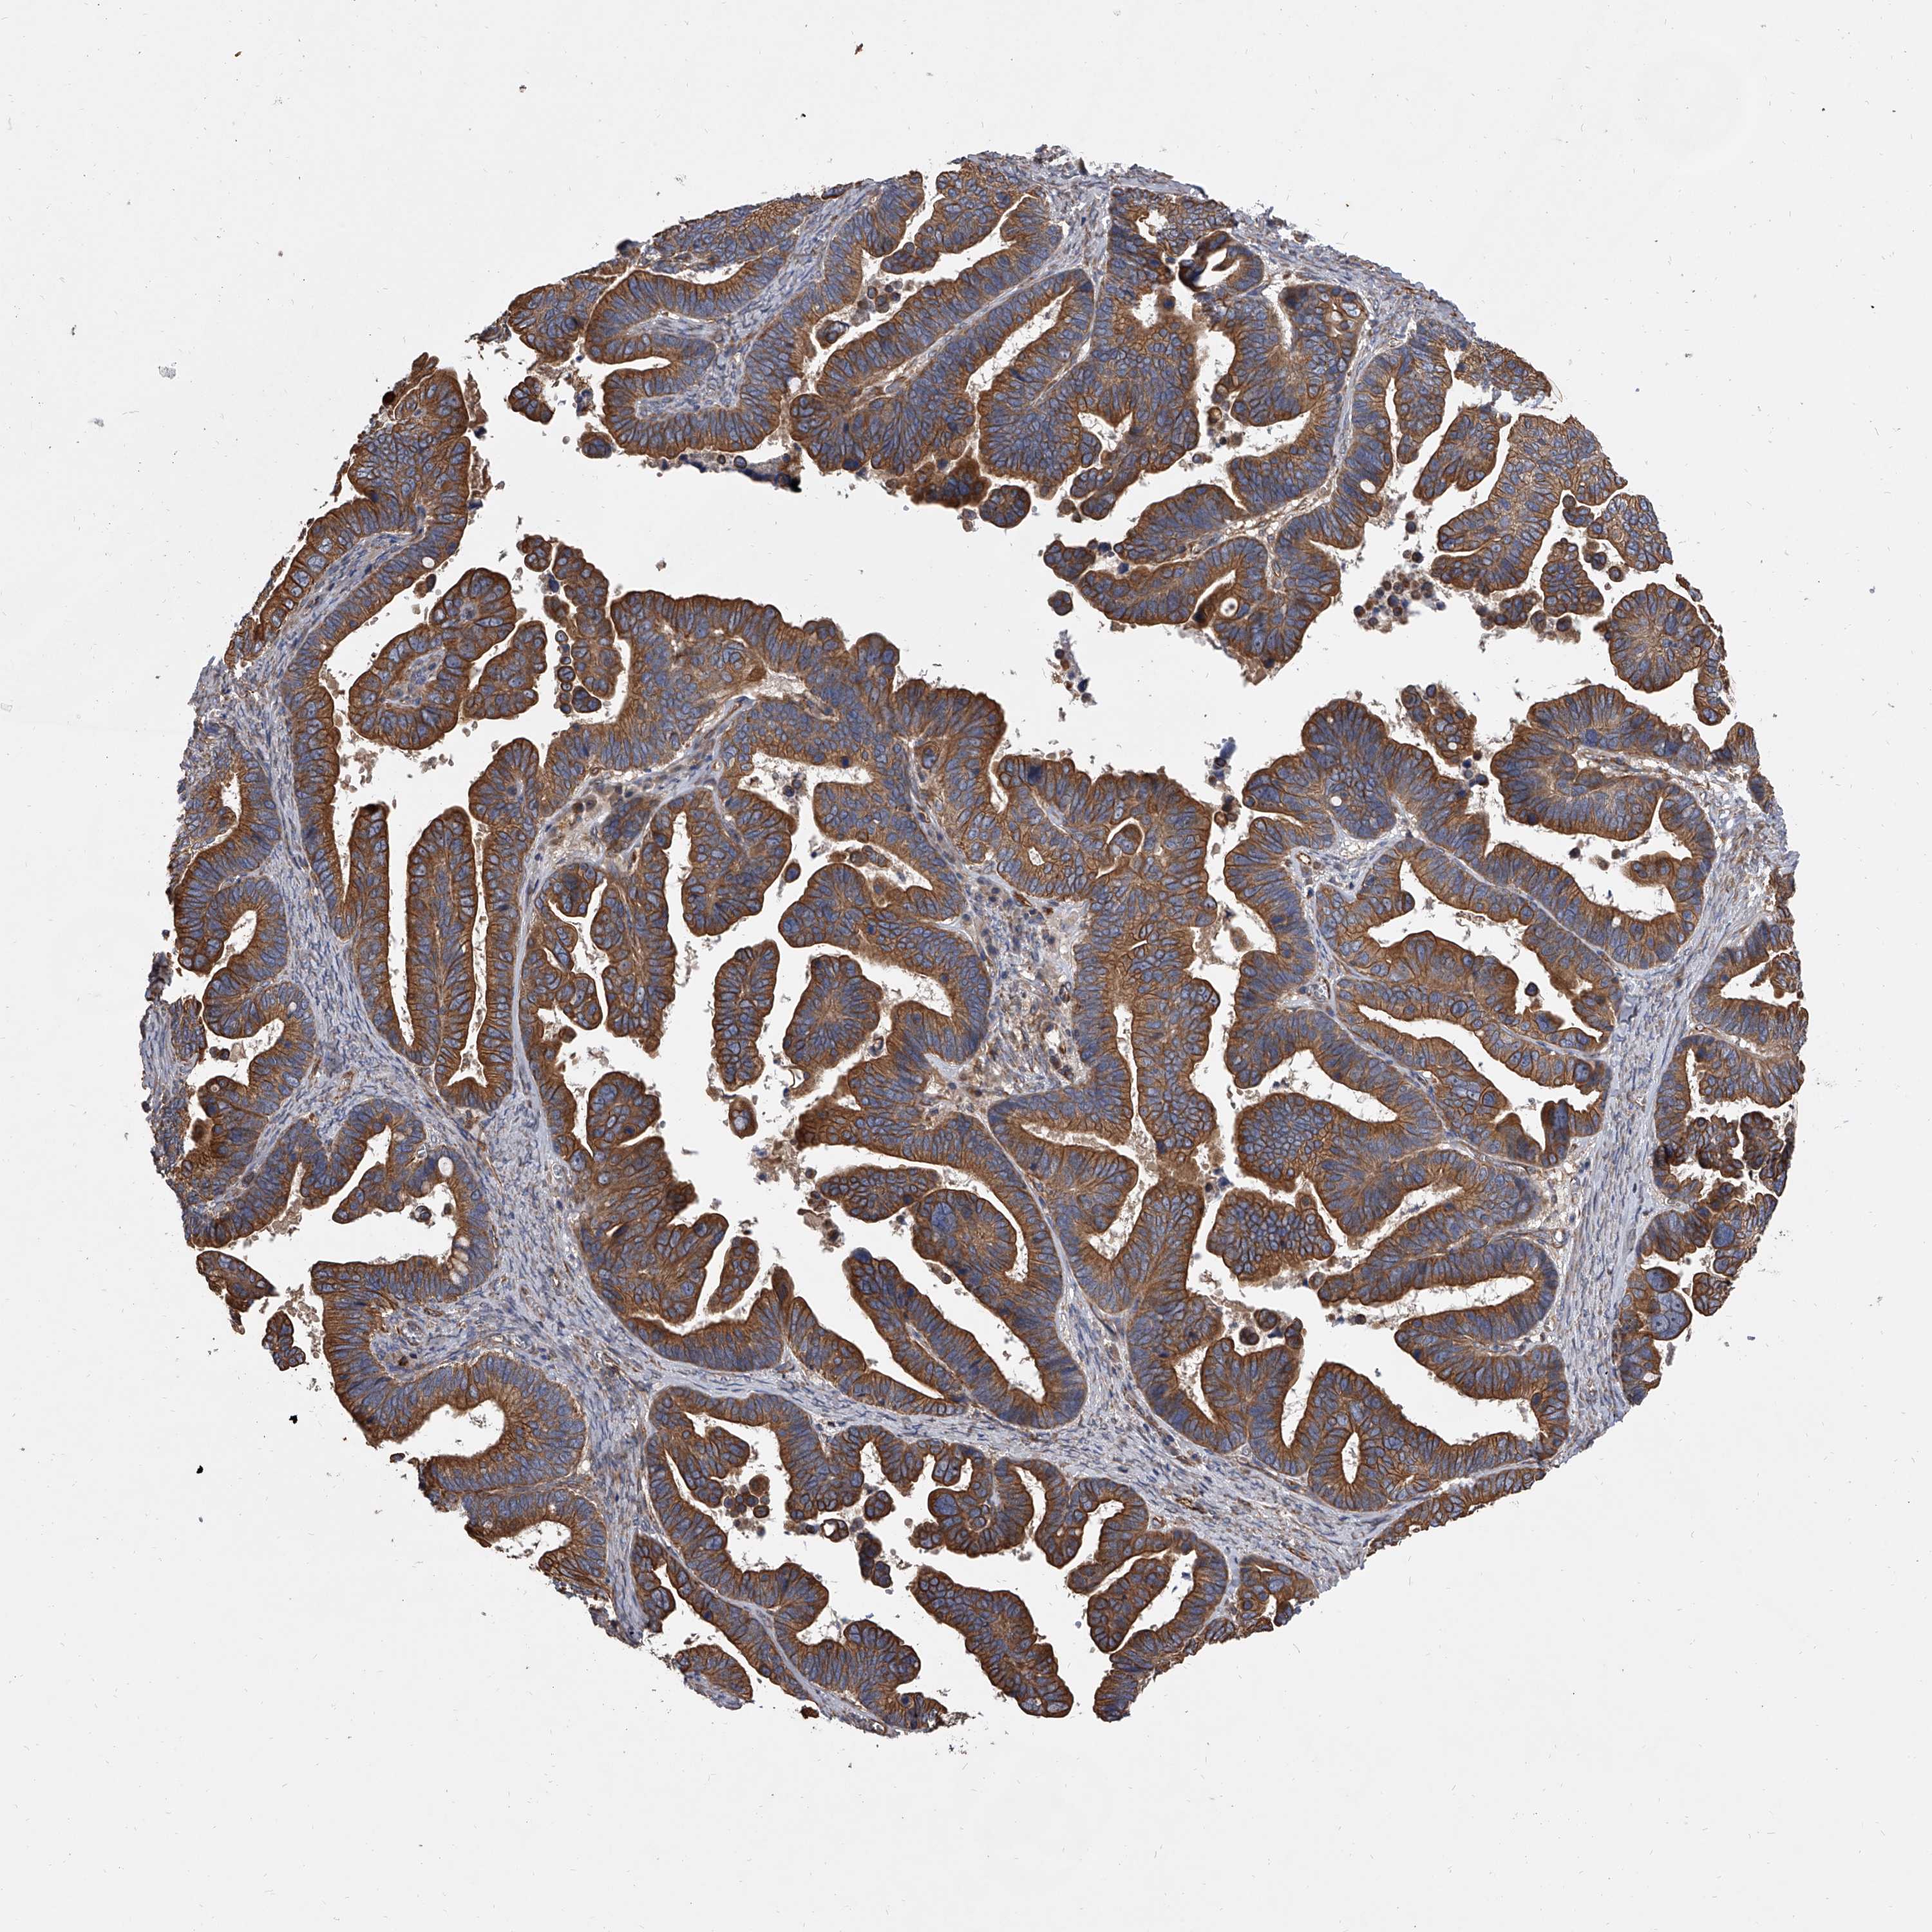

OVARIAN CANCER - Protein expressioni

A mouse-over function shows sample information and annotation data. Click on an image to view it in a full screen mode. Samples can be filtered based on level of antibody staining by selecting one or several of the following categories: high, medium, low and not detected. The assay and annotation is described here.

Note that samples used for immunohistochemistry by the Human Protein Atlas do not correspond to samples in the TCGA dataset.

Antibody stainingi

Antibody staining in the annotated cell types in the current human tissue is reported as not detected, low, medium, or high, based on conventional immunohistochemistry profiling in selected tissues. This score is based on the combination of the staining intensity and fraction of stained cells.

Each image is clickable and will lead to virtual microscopy that enables deeper exploration of all samples and also displays staining intensity scores, fraction scores and subcellular localization as well as patient and tissue information for each sample.

Antibody HPA031443

Staining

High

Medium

Low

Not detected

Intensity

Strong

Moderate

Weak

Negative

Quantity

>75%

75%-25%

<25%

None

Location

Nuclear

Cytoplasmic/membranous

Cytoplasmic/membranous,nuclear

Cystadenocarcinoma, serous, NOS

Carcinoma, endometroid

Cystadenocarcinoma, mucinous, NOS

Carcinoma, NOS